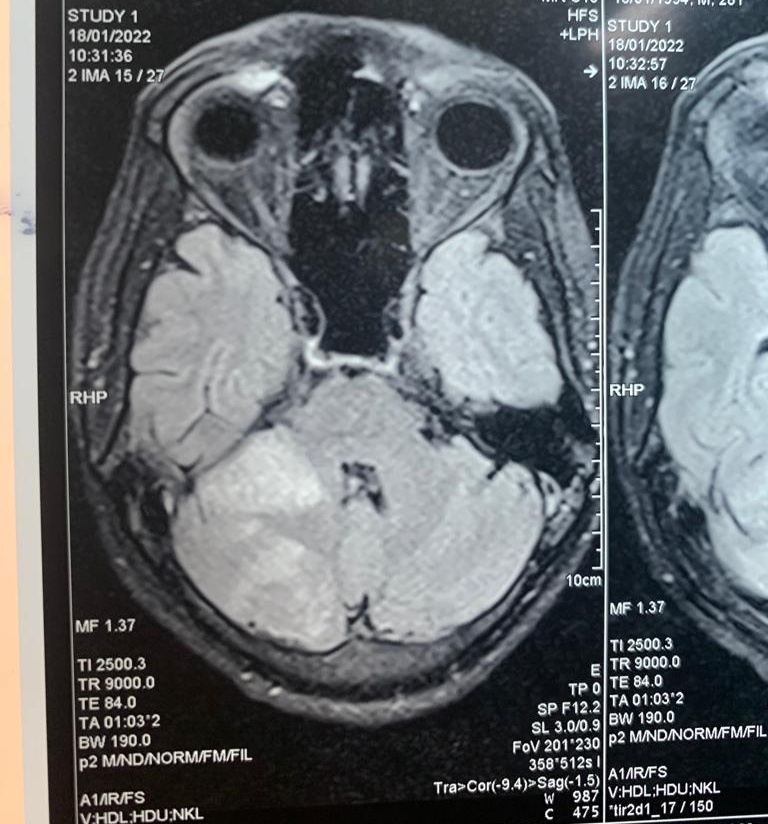

MRI BRAIN PLAIN WITH MR VENOGRAM AND MRI ANGIOGRAM

IMPRESSION :

1.SUB ACUTE INFARCTS IN THE RIGHT THALAMUS,RIGHT CEREBELLAR HEMISPHERE AND RIGHT SUPERIOR CEREBELLAR PEDUNCLE WITH HEMORRHAGIC TRANSFORMATION IN RIGHT SUPERIOR CEREBELLAR INFARCT - LIKELY EMBOLIC INFARCTS

2.LOSS OF NORMAL FLOW VOID SIGNAL IN LEFT TRANSVERSE SINUS AND PROXIMAL PART OF LEFT SIGMOID SINUS WITH FEW SURROUNDING COLLATERALS - S/O CHRONIC THROMBUS.

3.NORMAL MR ANGIOGRAM STUDY